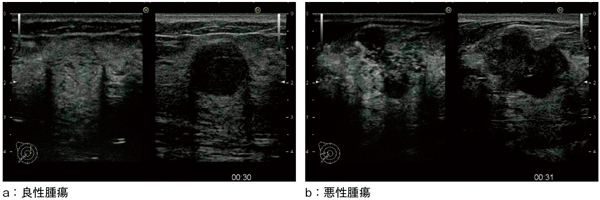

図3に,「HI VISION Ascendus」(図4)で撮像した乳腺造影の画像例を示す。良性腫瘍は腫瘤全体が均一に染影されているのに対し,悪性腫瘍は腫瘤全体が不均一に染影されており,腫瘤内のバブルは,非常に細かく表現されているとの評価を得ている。

図3 乳腺造影の画像例

(画像ご提供:りんくう総合医療センター外科・位藤俊一先生)